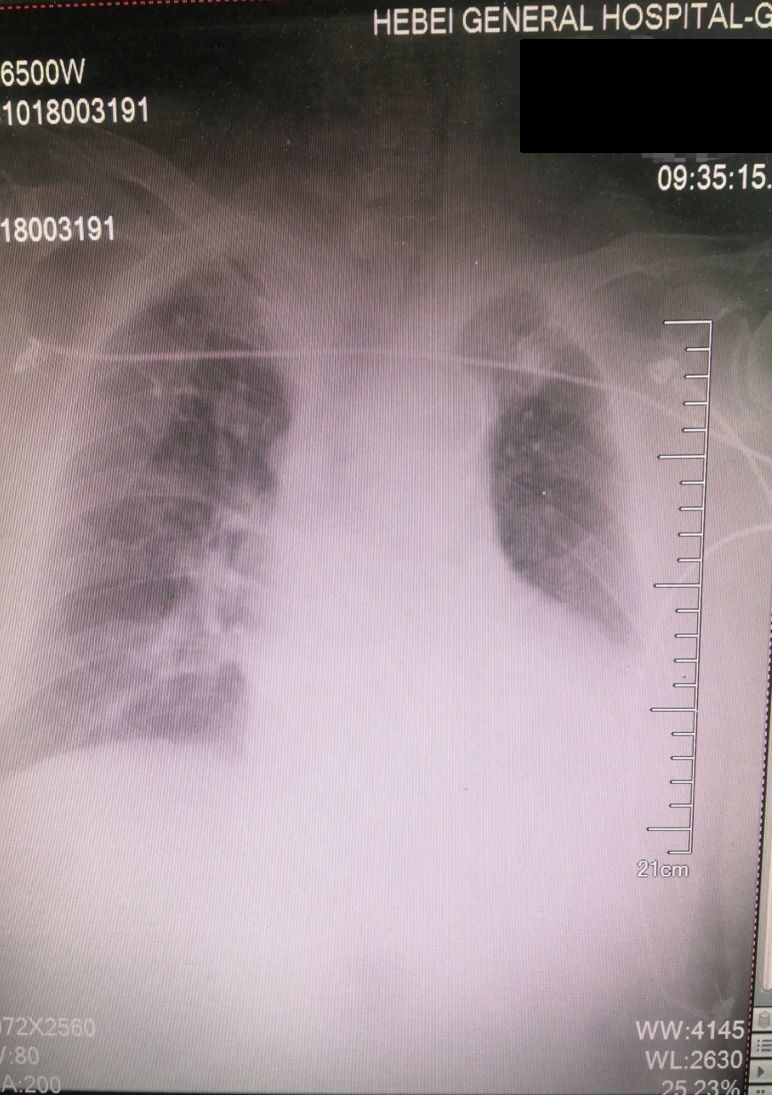

入院